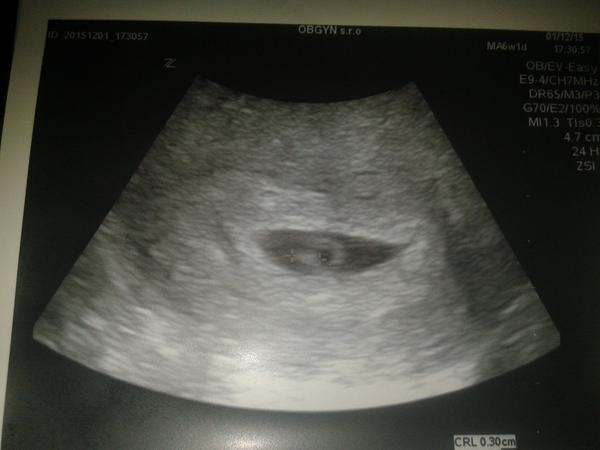

Dievčatá ja mam slabo .. Krémovo hnedý výtok uz od nedele ... Doktor povedal ze sa nemám znepokojovať , ale nevysetril ma zo spodu. Urobil mi ultrazvuk, ale takmer nic nebolo vidno ... Tak sa začínam báť. Som asi v 5tt. Stalo sa Vám to niekedy ze ste mali taký slabý krémovo hnedý výtok .. Farby ako biela káva ..?